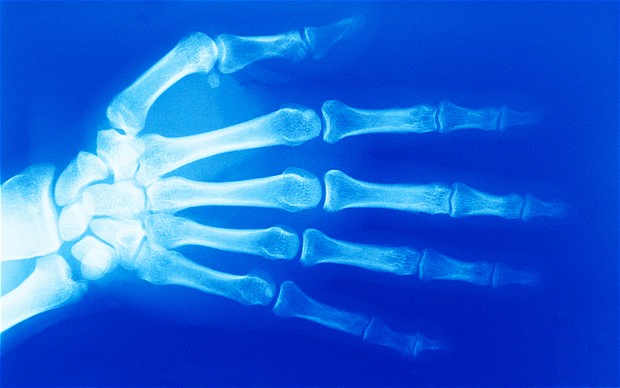

研究人員目前在骨骼、脂肪和軟骨等干細胞中都發現了結核病菌存在的痕跡。

此外,研究人員還在骨骼、脂肪和軟骨等干細胞中也都發現了結核病菌存在的痕跡。研究人員介紹說,干細胞具有修復和轉化成受損的細胞的功能,因此當肺部受傷或發炎時,干細胞就可能會“遷移”到病灶處,而潛伏在其中的結核病菌也會“殺”回肺部,因此干細胞是結核病菌“寄居”的理想環境。